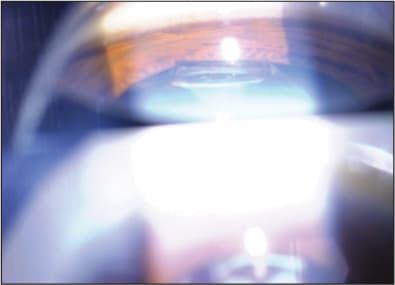

This is a 50-year-old biomedical engineer who presented with bilateral Z syndrome after cataract surgery with Crystalens done elsewhere one year earlier. He is a very high myope with long, 29.8-mm eyes who received 6 D implants. In both eyes, I saw severe fibrosis, posterior capsule haze and a Z syndrome (Figures 1 and 2) with the lens pushed forward to the point that it was actually anterior the pupil plane on gonioscopy (Figure 3). The Z syndrome had induced significant myopia and astigmatism and the capsular haze limited BCVA to 20/60 OD and 20/100 OS.

Figure 3. Gonioscopic view of left eye showing severe elevation of inferior haptic above iris plane.